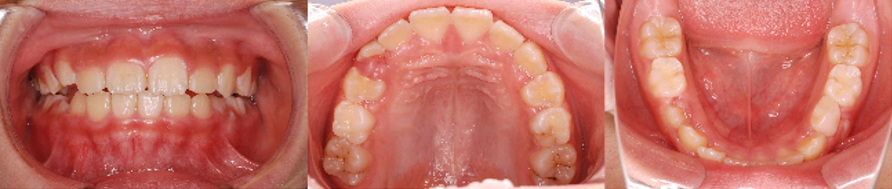

1.8歳女児の症例

トレーナー(K1)とアクティビティをほとんど皆勤賞で頑張っている子です。家族みんなに協力していただいているため、わずか5ヶ月でここまできました。なお、途中BWS装置により2ヶ月間前方拡大を行っています。

今後、嚥下などのアクティビティが残されているため、アクティビティを完結させるとこまで目指しています。

初診時

半年後